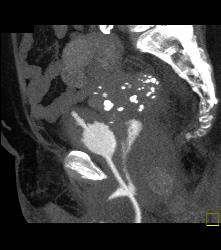

Bladder Fistulae